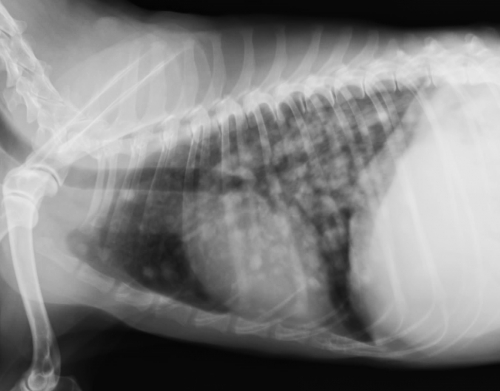

下の写真が肺転移の一例です。(右写真が正常です。)